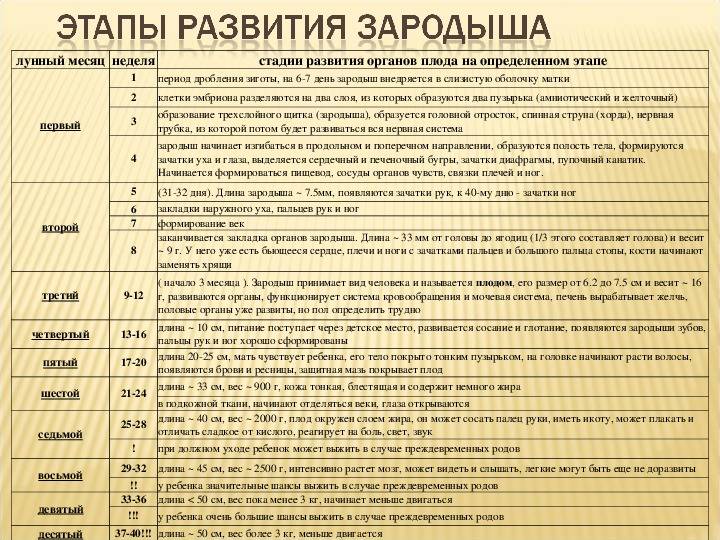

По окончании второго триместра будущая мамочка выходит на финишную прямую. Впереди только роды и счастливые годы материнства. Таких крупных перемен уже не будет, каждый следующий месяц ребенок будет все больше и больше готовиться к появлению на свет: набирать вес (в 9 месяцев ребенок весит – более 3 килограмм), сформируется его собственная система регуляции тепла, которая не даст ему замерзнуть при появлении на свет, окончательно разовьются легкие, чтобы позволить малышу легко перейти к новому виду дыхания.

16 недель. Ребенок весит примерно 150 граммов, его рост достигает 16-18 сантиметров. На головке появляются волосы, на лице — реснички и брови. Малыш открывает ротик, глотает, сосет, улыбается. В этот период начинает полноценно функционировать плацента, которая связывает его с мамой.

20 недель. Рост малыша достигает 30 сантиметров, у него появляются ноготки на пальцах рук и ног. Теперь мама чувствует его движения, так как время от времени он начинает заниматься физкультурой: отталкивается от одной стенки матки и доплывает до другой. Кроме того, ребенок может отреагировать на резкий звук или волнение матери прыжком, который воспринимается как активное шевеление. Если же малыш начинает икать, женщина ощущает слабые ритмичные толчки, идущие изнутри. В 20 недель врачи выслушивают сердцебиение малыша с помощью стетоскопа.

24 недели. Малыш уже может рассердиться. Это доказывает фотография ребенка в этом возрасте. На ней видны его сердитый взгляд, напряжение мышц вокруг глаз, сморщенные губки, видно, что он плачет, выражая свое недовольство. Кстати, чтобы отдохнуть ночью, малыш ложится спать и… видит сны. Ребенок весит около 500 граммов это немного, но он только начал набирать вес. Его кожа красная и морщинистая. Так как она еще очень нежна, малыш защищается от воздействия околоплодных вод специальной смазкой. К 24-й неделе беременности начинают функционировать жировые и потовые железы, созревают легкие ребенка. В них образуется пленка, которая не дает им склеиваться при дыхании. Если ребенок родится в это время и будет обеспечен необходимой заботой, он сможет выжить.

8-й месяц: 29-32 недели

С каждым днем ребенок все больше и больше подготавливается к предстоящей жизни вне организма мамы и родам. Он уже весит около 1,5-1,6 килограмма и достигает в длину 40 сантиметров. Сейчас он занимает почти все место в матке, поэтому движения его очень рациональны. Он уже не «плавает», а совершает более точные движения ручками и ножками.

В течение 8-го месяца ребенок занимает то положение, в котором он будет в родах.

В 96% случаев – это головное предлежание – то есть ребенок располагается строго головой вниз, бывает также тазовое предлежание – когда он занимает позицию попкой или ножками к выходу из малого таза, а также поперечное предлежание – когда он лежит поперек продольной оси матки.

Самым лучшим для естественных родов, конечно, является головное предлежание, но на 8-м месяце предлежание ребенка еще может поменяться само или с помощью специальных упражнений. Однако, если он уже устроился (головное предлежание), можете одевать бандаж, чтобы закрепить такое положение.

Ваш доктор, используя специальные приемы пальпации – приёмы Леопольда, может очень легко определить положение плода.

На 8-м месяце продолжают формироваться альвеолы легких, увеличивается количество сурфактанта.

Почти полностью формируется сердце и кровеносная система: между правым и левым предсердием пока остается отверстие (баталлов проток), поэтому в венах и артериях ребенка течет смешанная кровь. Это отверстие закроется уже после рождения.

10-й месяц: 37-40 недель

Не переживайте если ребенок не родился на 9-м месяце, у него еще есть время. Рождение в 37-42 недель абсолютно естественно и нормально. Вы должны довериться в этом ребенку и своему мудрому организму, они сами подберут наилучшее время.

Итак, на 10-м месяце все системы ребенка готовы к рождению. Работает пищеварительный тракт: ворсинки кишечника продвигают первородный кал вниз к толстому кишечнику, работает желудок, поджелудочная железа вырабатывает пепсин, необходимый в пищеварении.

Однако пищеварительная система ребенка в утробе абсолютно стерильна, все нужные бактерии, которые помогают переваривать и усваивать пищу появятся только в период лактации из грудного молока матери.

Заканчивает развитие половая система – у девочек большие половые губы закрывают маленькие, у мальчиков яички в большинстве случаев опускаются в мошонку.

Надпочечники настолько увеличиваются в размерах, что становятся больше почек, так как на их долю приходится выработка гормонов стресса во время родов – адреналина и норадреналина.

Кости черепа и швы остаются мягкими и податливыми. 2 родничка – теменной и затылочный помогают черепу принять удобную форму, чтобы пройти по родовым каналам матери без травм.

11-20 недели

11 неделя

Критический этап развития фактически закончен. Вес плода достигает 8 г, «рост» – 5 см. С этого момента эмбрион переходит в стадию плода. Сердце работает полноценно, завершается формирование кровеносных сосудов. Плацента становится плотной. Печень занимает 10% тела. Кишечник совершает первые движения, подобные перистальтике.

12 неделя

Критические моменты для развития плода больше зависят от здоровья и образа жизни мамы. Длина тела колеблется в пределах 6-9 см. Будущий ребенок уже имеет пальцы, образовываются ногти. Органы ЖКТ заканчивают формирование. Совершенствуется иммунная система.

13 неделя

Первый триместр заканчивается, критический цикл завершен. Полностью заложены молочные зубы, продолжает оформляться мышечная, костная ткань, развивается пищеварительная система. Дифференцируются половые органы. «Рост» ребенка достигает 8 см, вес – 15-25 г.

14 неделя

Малыш активно растет и развивается. Его вес равен 30-40 г, а рост – от 8 до 10 см. Схожесть с человеком все больше. При условии многоплодной беременности будущая мама может почувствовать движения детей, которые становятся все активнее. Костный скелет наращивается, формируются ребра. Движения диафрагмы напоминают дыхательные. Все органы, системы полностью сформированы. У ребенка есть резус-фактор и группа крови.

15 неделя

Начиная с 15 недели, у ребенка начинает формироваться кора головного мозга. Процесс займет большую часть второго триместра. Активизируется эндокринная система, сальные, потовые железы.

Полностью сформированы вкусовые рецепторы, совершенствуются дыхательные движения. Вес ребенка достигает 70 г, от копчика до темени он уже целых 10 см. Но даже при условии многоплодной беременности это не мешает свободным движениям.

16 неделя

К первой половине второго триместра малыш уже 11 см ростом, а весом – 120 г. Шея заняла ровное положение, голова свободно вращается. Уши и глаза постепенно поднимаются вверх. Печень перебирает на себя пищеварительные функции. Календарь развития становится насыщеннее. Состав крови полностью сформирован.

17 неделя

Включается иммунная система, продуцируется интерферон, иммуноглобулин. Малыш способен защищаться от инфекций, поступающих от мамы. Но все они продолжают быть критическими для маленького организма. У плода появляется жировая прослойка. Если растет девочка, к середине второго триместра у нее появляется матка. Рост человека – 13 см, вес – 140 г. Он способен слышать звуки извне, ощущать эмоции

С точки зрения эмоционально-психического развития 17 неделя критическая – устанавливать контакт крайне важно

18 неделя

Второй триместр приближается к середине. Полностью сформированы верхние и нижние конечности плода, фаланги пальцев, отпечатки на них. Жировая ткань, иммунная система и головной мозг на 18 неделе продолжают активно развиваться. Формируются зачатки коренных зубов.

19 неделя

Наблюдается большой скачок в развитии. Движения становятся более упорядоченными. Дыхательная система совершенствуется. Тело покрывается первородной смазкой. К 19 неделе голова свободно вращается, удерживается в одном положении. Вес достигает 250 г, а рост – 15 см.

20 неделя

Ребенок уже полностью сформирован, его органы совершенствуются. К 20 неделе сердцебиение может быть расслышано обыкновенным стетоскопом. Конечности полностью сформированы. Ощущения звуков становятся более острыми. Длина составляет 25 см, а вес – около 340 г. Движения более ощутимы для мамы.